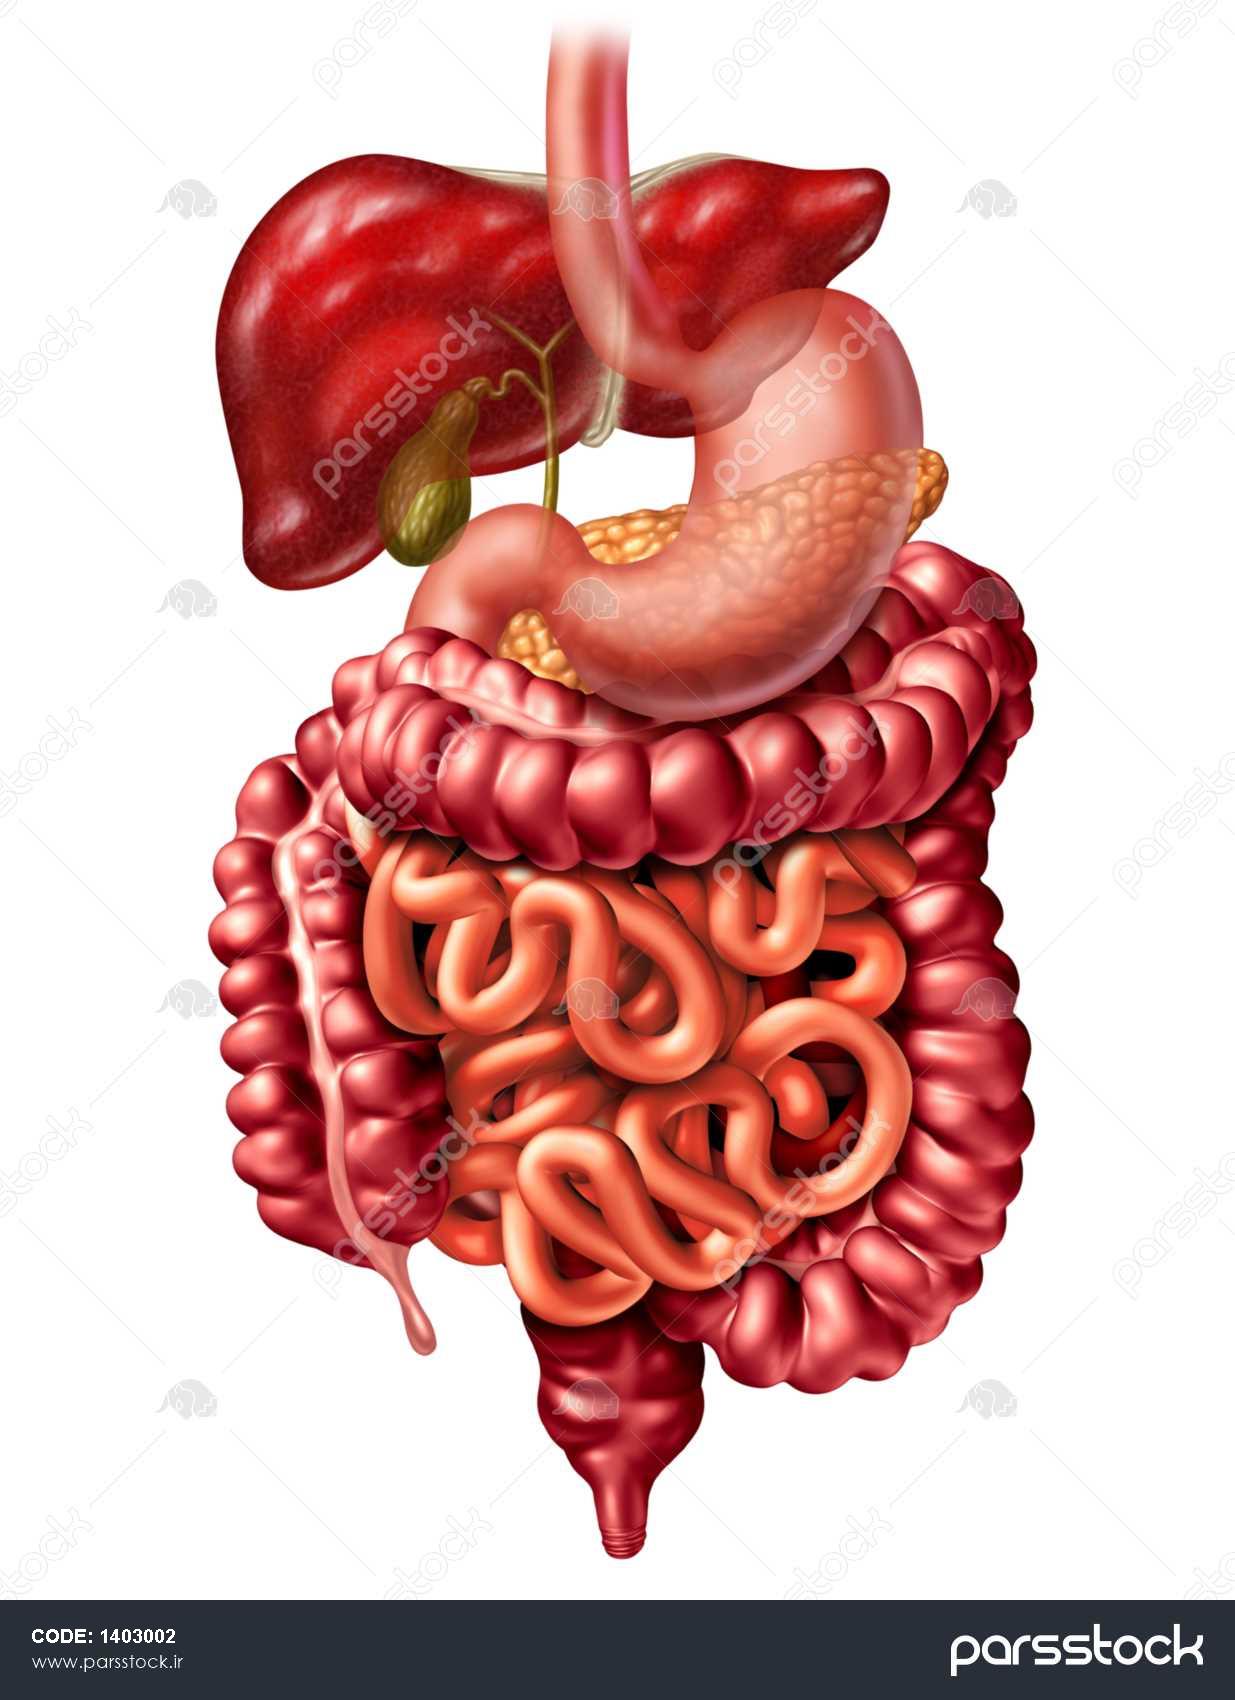

عکس اسکلت بدن انسان با کیفیت. عکس اسکلت عکس اسکلت برای پروفایل عکس اسکلت انسان عکس اسکلت خفن عکس اسکلت بدن انسان با کیفیت عکس اسکلت بدن انسان عکس اسکلت ترسناک عکس اسکلت فانتزی عکس اسکلت فانتزی دخترانه پرچم عکس اسکلت. عکس با کیفیت اسکلت داخلی انسان و درد و گرفتگی در ناحیه استخوان زانو ویژه استفاده در امور تبلیغاتی و تجاری طراحی کاتالوگ بروشور و تراکت با موضوع پزشکی فیزیوتراپی ارتوپد دکتر روماتیسم فیریوتراپ طب فیزیکی. عکس اسکلت بدن انسان زن و مرد آناتومی ساتین 16 سپتامبر 2017. اسکلت داربست بدن است تمام قسمت های بدن روی اسکلت قرارگرفته اند بدن انسان از ۲۰۶ قطعه استخوان تشکیل شده است این استخوان ها طوری با نظم کنار هم قرار گرفته اند که انسان را قادر می سازد حرکات دقیقی داشته باشد.

اسکلت جمجمه و گردن انسان ستون فقرات آناتومی اسکلت جمجمه و گردن انسان ستون فقرات آناتومی تصویر با کیفیت را از لینک زیر می توانید دانلود کنید. ۱ مطلب با کلمه ی کلیدی عکس اسکلت بدن انسان با کیفیت ثبت شده است گالری نسیم جدید ترین و با کیفیت ترین عکس های مناسبتی. عکس با کیفیت آناتومی اسکلت بدن انسان و درد و دیسک در قسمت مهره های ستون فقرات کمر ویژه استفاده در امور تبلیغاتی و تجاری طراحی کاتالوگ بروشور و تراکت با موضوع بیمارستان ها و کلینیک ها و درمانگاه ها و مطب ها پزشکان و.